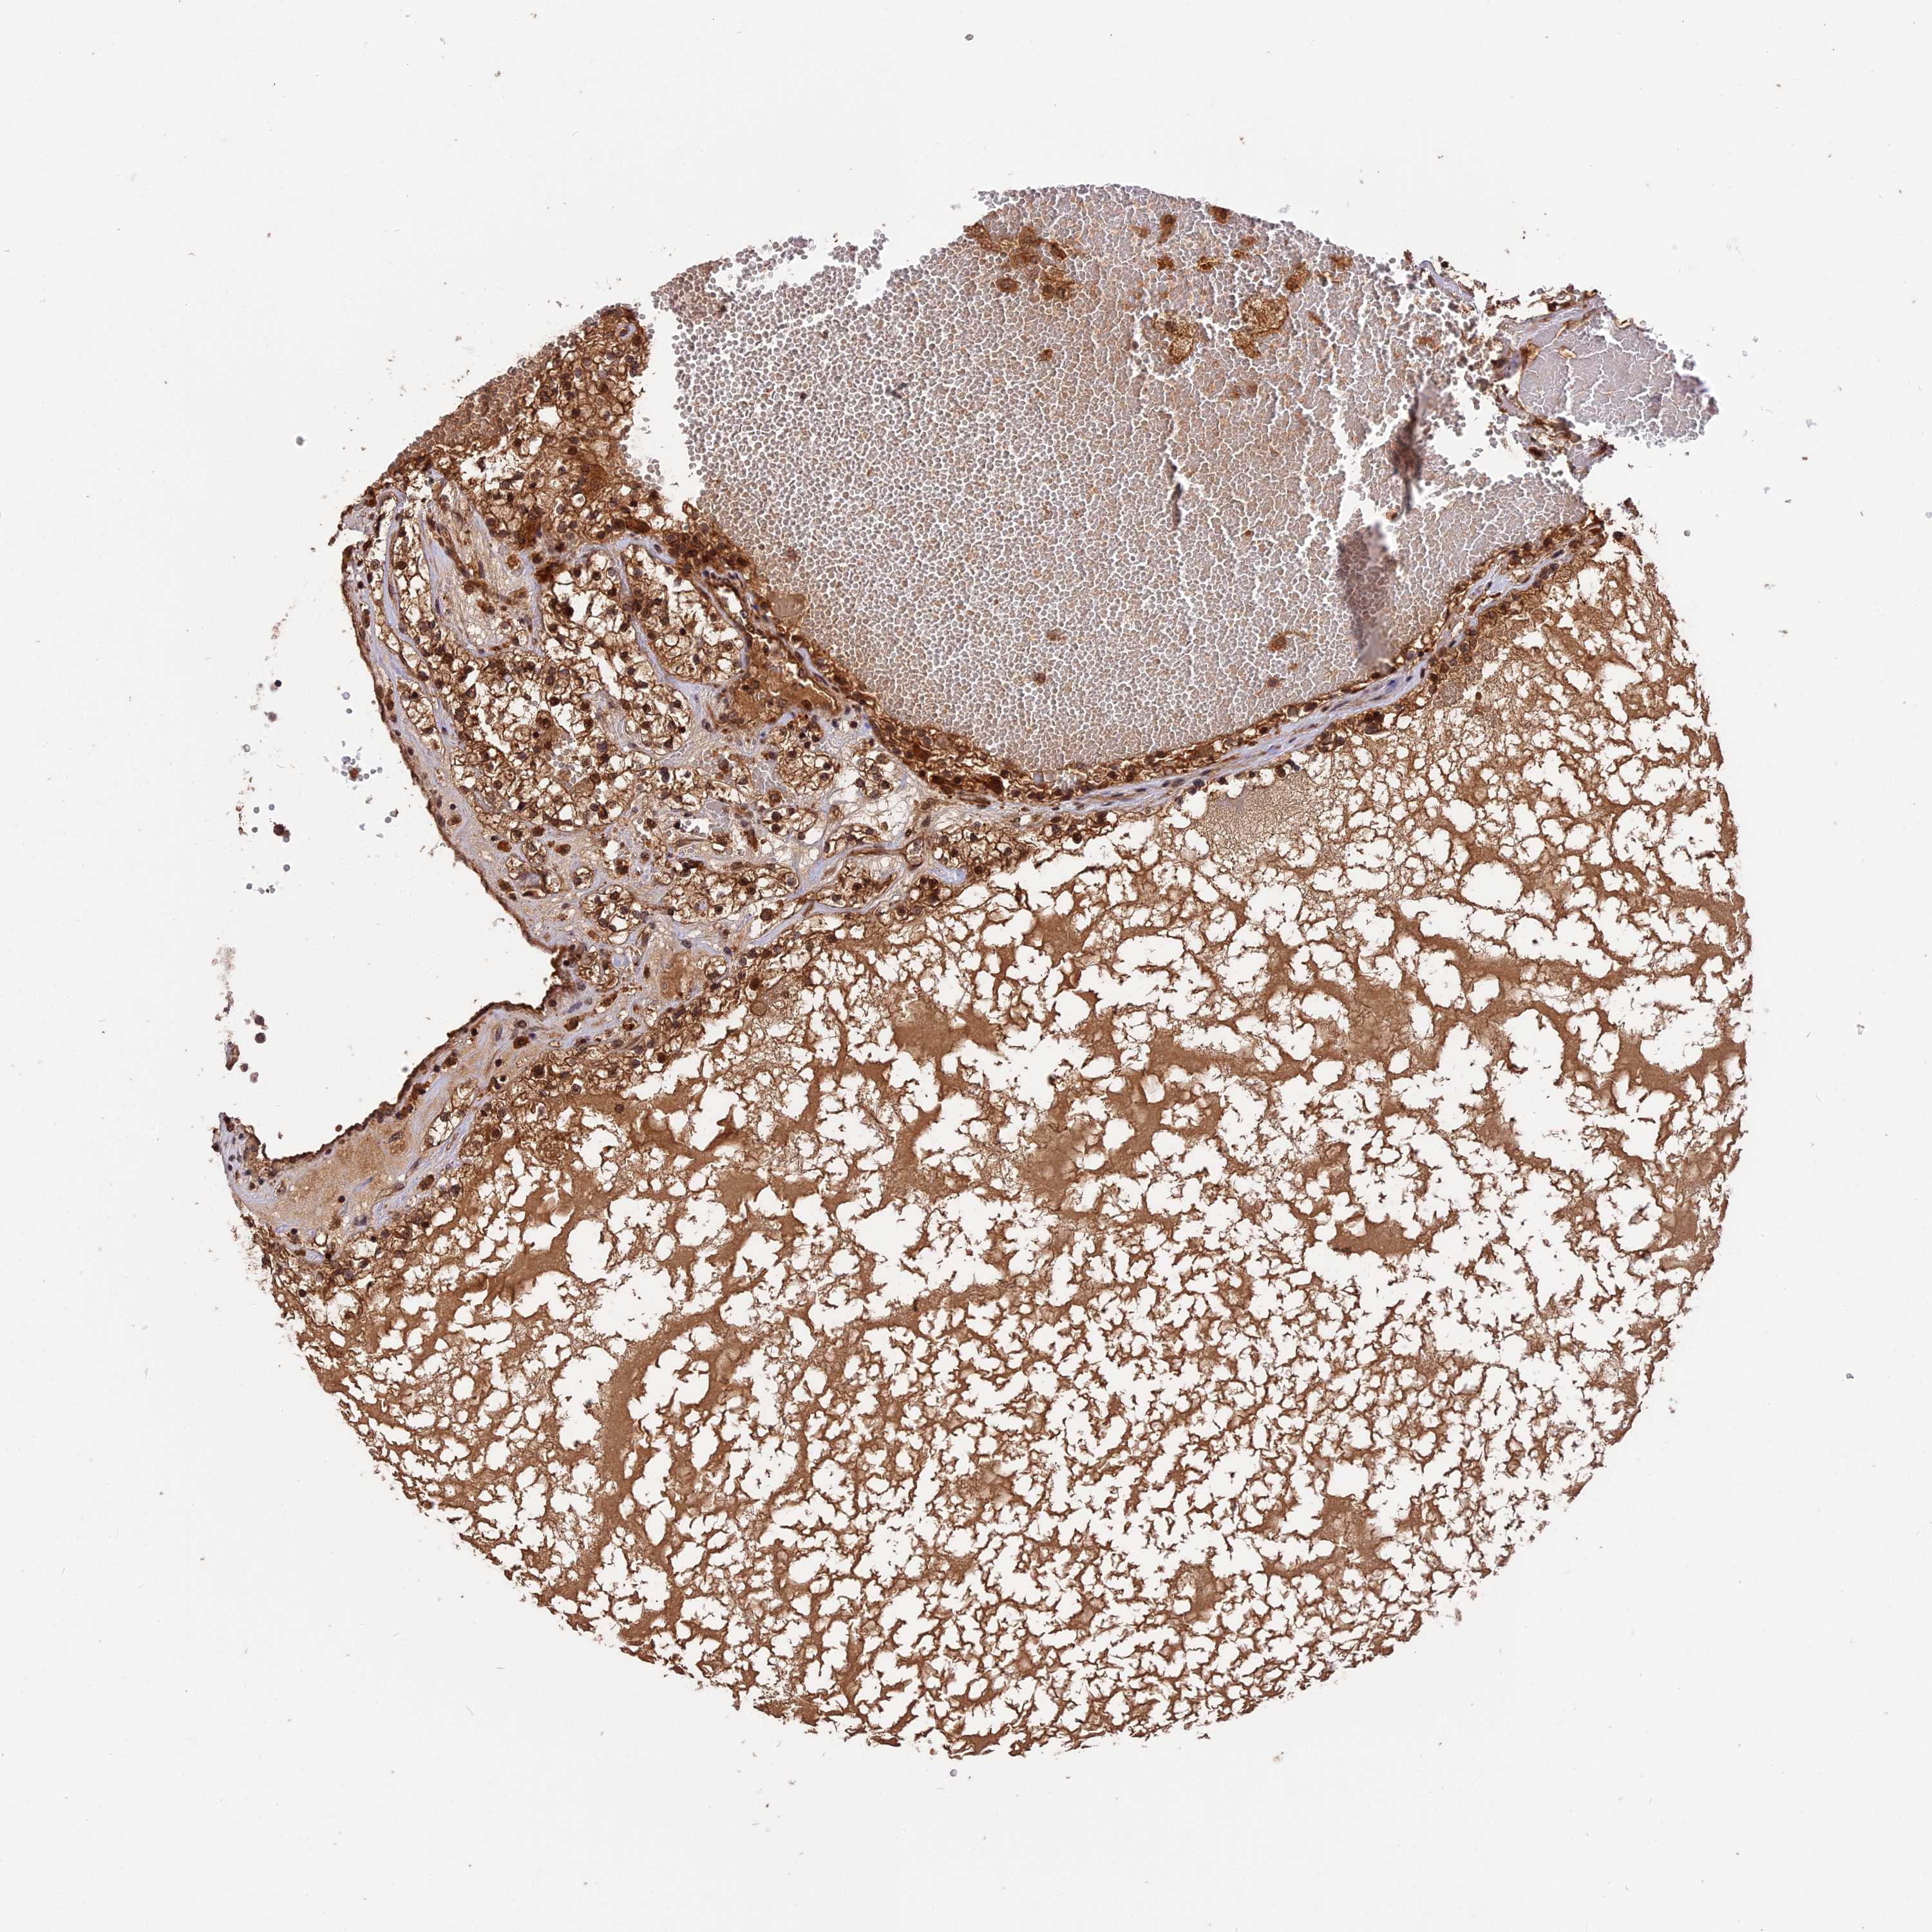

TCGA RNA samplesi

RNA-seq data is reported as average FPKM (number Fragments Per Kilobase of exon per Million reads), generated by the The Cancer Genome Atlas (TCGA) .

Normal distribution across the dataset is visualized with box plots, shown as median and 25th and 75th percentiles. Points are displayed as outliers if they are above or below 1.5 times the interquartile range. FPKM values of the individual samples are presented next to the box plot.

Average pTPM 7.2